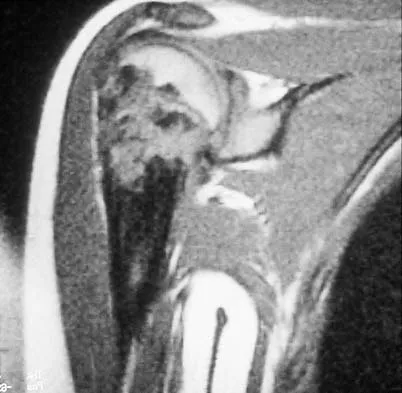

Figure 47 shows a transverse MRI scan of a patient's left shoulder. The findings reveal which of the following abnormalities?

Explanation

The MRI scan shows a defect in the posterior aspect of the humeral head, commonly referred to as a Hill-Sachs lesion. This is an impaction fracture of the humeral head that occurs during anterior shoulder dislocation. The abnormality on this image is an irregularity of the posterior humeral head; the humeral head otherwise has a homogenous appearance. The coracoid, subscapularis, and posterior labrum are normal. Griffin LY (ed): Orthopaedic Knowledge Update: Sports Medicine. Rosemont, IL, American Academy of Orthopaedic Surgeons, 1994, pp 47-63.